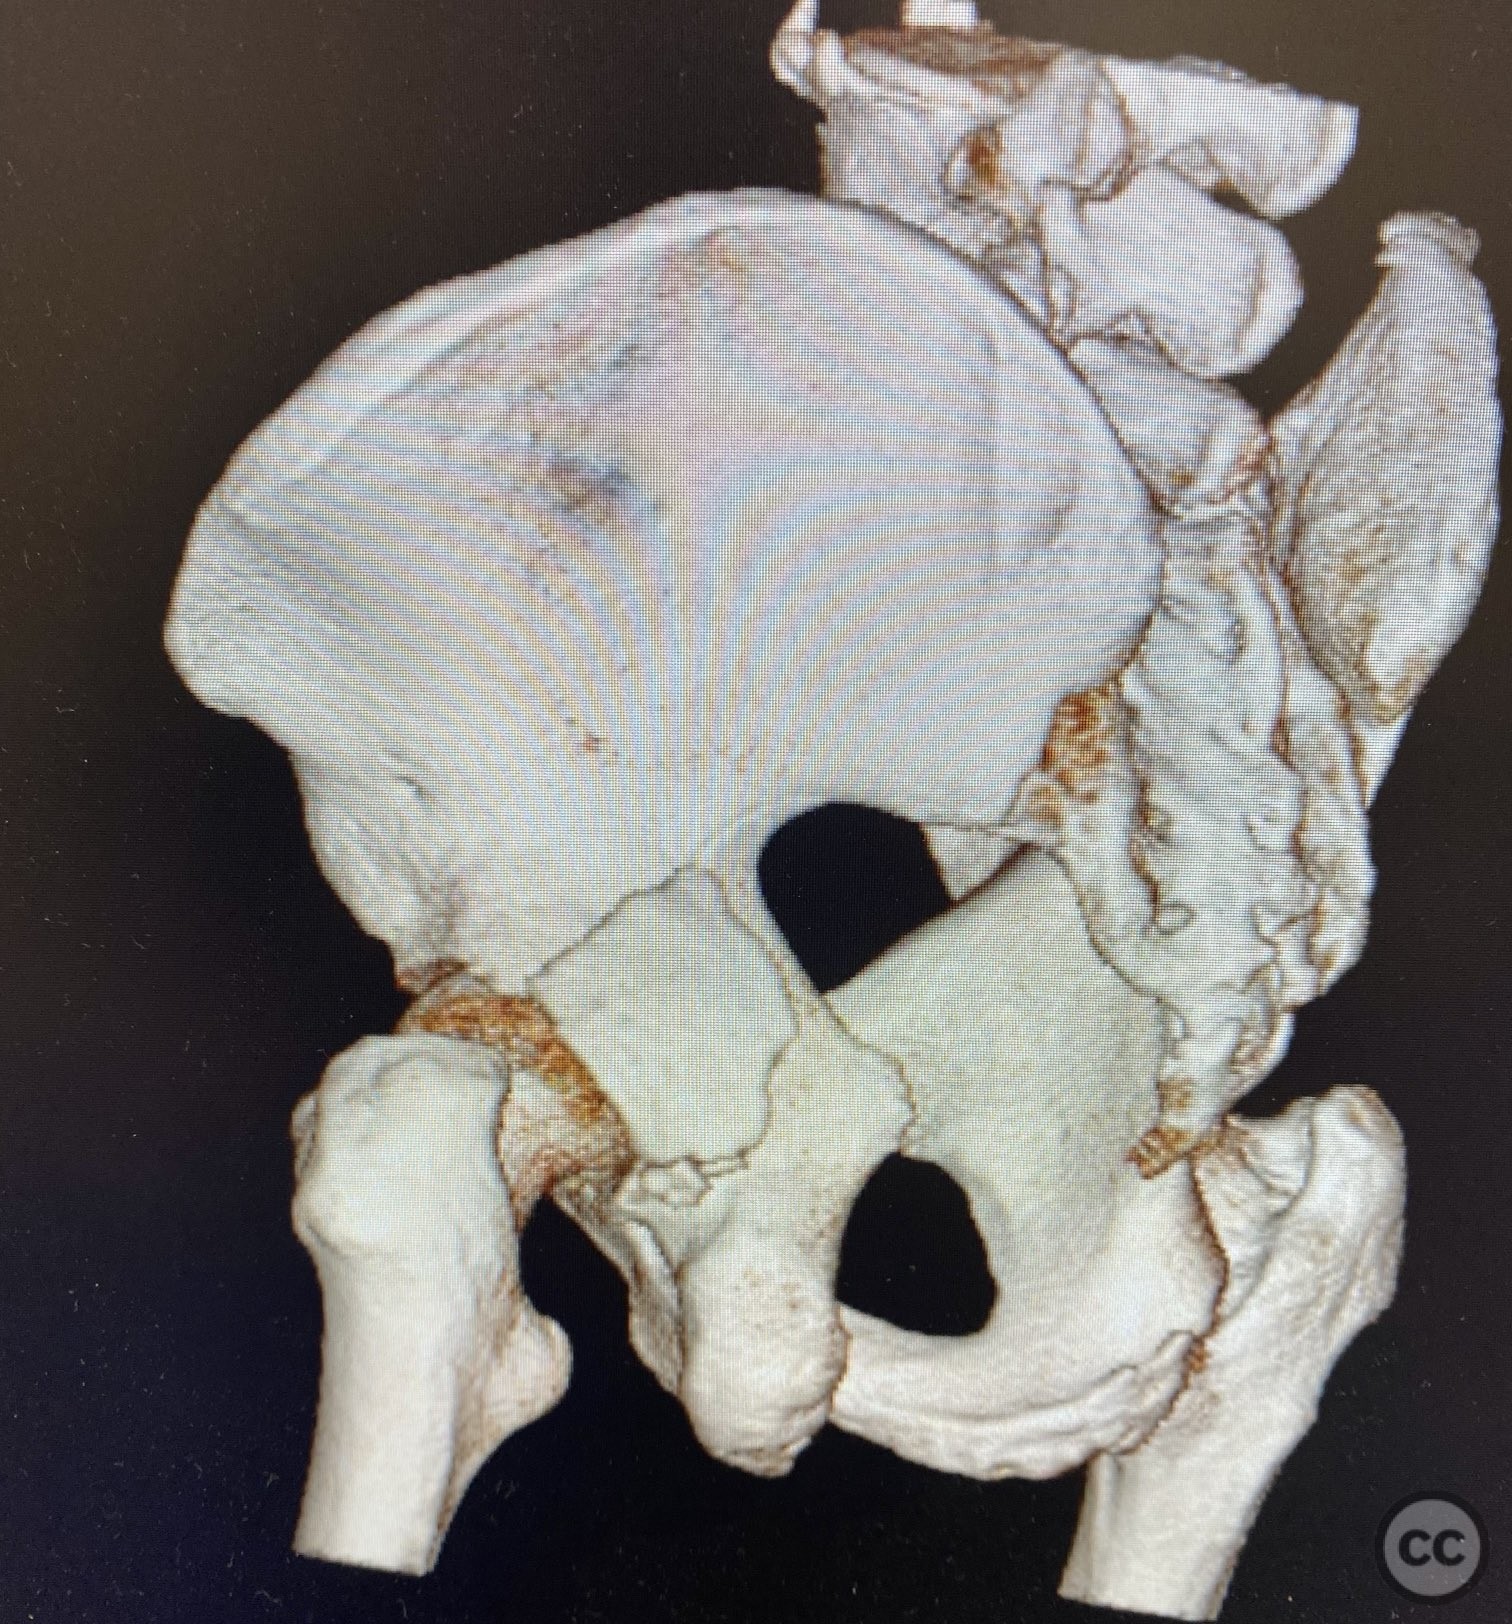

Clinical and radiological findings:  A patient presented with a seemingly non-comminuted, wide, and long posterior wall (PW) acetabular fracture fragment. Axial computed tomography (CT) images demonstrated the thickness of the PW fragment, the articular surface, and multiple areas of subchondral impaction. Preoperative planning identified the size, location, and depth of the impaction zones, as well as an essentially nondisplaced transverse acetabular fracture line, which was not readily apparent on initial imaging. No significant displacement of the transverse component was noted. The AO/OTA classification is 62-B1.3 (posterior wall and transverse acetabular fracture).

Planning remarks:  The preoperative technical plan included a prone Kocher-Langenbeck (KL) approach to access the posterior column and wall. The plan entailed elevation and reduction of impacted articular fragments, bone grafting of subchondral defects, anatomical reduction and provisional fixation of the posterior wall fragment, and definitive fixation with a contoured plate. Intraoperative fluoroscopy was planned to guide additional screw placement through the plate to stabilize both the posterior wall and the transverse fracture line. A supplementary medial plate was planned to augment fixation of both the posterior wall and transverse components.

Intraoperatively, elevation and reduction of impacted articular fragments were performed, followed by bone grafting of subchondral defects. The posterior wall fragment was anatomically reduced and initially stabilized with a contoured plate. Intraoperative fluoroscopy (obturator oblique view) was utilized to guide placement of an additional screw through the plate above the joint, traversing both the posterior wall fragment and stabilizing the transverse fracture line. A supplementary medial plate was applied to further support both fracture components. Postoperative CT imaging confirmed satisfactory reduction of both the posterior wall and transverse fractures, as well as restoration of articular congruity in previously impacted areas. Consideration is given to whether initial reduction and lag screw fixation of the transverse component prior to plate application may have improved reduction; however, final imaging demonstrated acceptable alignment.